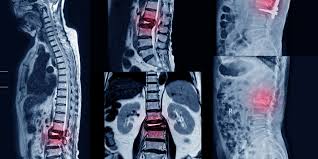

Los AINE y la teriparatida pueden ser las opciones de tratamiento preferidas para el tratamiento del dolor agudo en las fracturas vertebrales por compresión osteoporóticas. Aunque la calcitonina también demostró ser beneficiosa, su perfil de seguridad y los posibles efectos adversos restringen su aplicación generalizada. La evidencia limitada sobre los aparatos ortopédicos y los analgésicos subraya la necesidad urgente de investigaciones futuras. JAMA Netw Open. 3 de septiembre de 2024